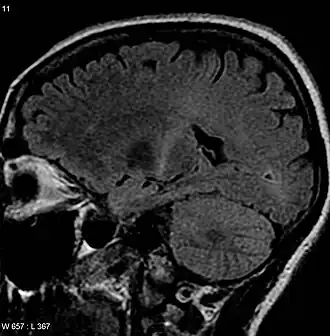

| Uma MRI com sinal aumentado na parte posterior da cápsula interna que pode rastrear o córtex motor que é consistente com o diagnóstico de ELA | |